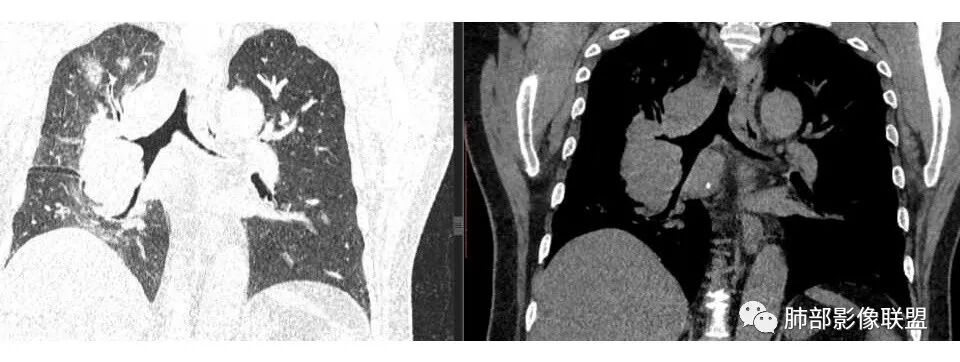

肺门及纵隔多发淋巴结。2L,4R,3区都有肿大淋巴结。

南边:有老师认为,血管前的这个应该是一个胸腺来源的。我觉得不是,为什么不符合胸腺来源呢,就看那个内乳动脉

双侧对比:右侧增粗,提示供血

但在内侧,不是外移

所以我倾向于淋巴结可能

胸腺瘤按理推压外移的多

而且胸腺癌转移不以淋巴结为主,如果淋巴结显著,按理周围侵袭性比较强,淋巴结也应该以附近为主,不应该以肺门为主,不符合引流规律。

1.右肺上叶不规则结节影,右肺门及纵隔多结节并形成巨大块影,密度均匀,沿途支气管明显狭窄。

原发灶小或隐匿,肺门纵隔淋巴结异常增大,所谓“娘小崽大”常见于肺小细胞癌!